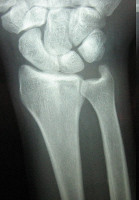

Οι απλές ακτινογραφίες συνήθως δεν είναι διαγνωστικές και απαιτείται διενέργεια μαγνητικής τομογραφίας για την επιβεβαίωση της κλινικής διάγνωσης.